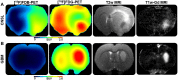

This paper investigated whether positron emission tomography (PET) imaging with [18F]fludarabine ([18F]FDB) can help to differentiate central nervous system lymphoma (CNSL) from glioblastoma (GBM), which is a crucial issue in the diagnosis and management of patients with these aggressive brain tumors. Multimodal analyses with [18F]fluorodeoxyglucose ([18F]FDG), magnetic resonance imaging (MRI) and histology have also been considered to address the specificity of [18F]FDB for CNSL. Methods: Nude rats were implanted with human MC116 lymphoma-cells (n = 9) or U87 glioma-cells (n = 4). Tumor growth was monitored by MRI, with T2-weighted sequence for anatomical features and T1-weighted with gadolinium (Gd) enhancement for blood brain barrier (BBB) permeability assessment. For PET investigation, [18F]FDB or [18F]FDG (~11 MBq) were injected via tail vein and dynamic PET images were acquired up to 90 min after radiotracer injection. Paired scans of the same rat with the two [18F]-labelled radiotracers were investigated. Initial volumes of interest were manually delineated on T2w images and set on co-registered PET images and tumor-to-background ratio (TBR) was calculated to semi-quantitatively assess the tracer accumulation in the tumor. A tile-based method for image analysis was developed in order to make comparative analysis between radiotracer uptake and values extracted from immunohistochemistry staining. Results: In the lymphoma model, PET time-activity curves (TACs) revealed a differential response of [18F]FDB between tumoral and healthy tissues with average TBR varying from 2.45 to 3.16 between 5 to 90 min post-injection. In contrast, [18F]FDG demonstrated similar uptake profiles for tumoral and normal regions with TBR varying from 0.84 to 1.06 between these two time points. In the glioblastoma (GBM) model, the average TBRs were from 2.14 to 1.01 for [18F]FDB and from 0.95 to 1.65 for [18F]FDG. Therefore, inter-model comparisons showed significantly divergent responses (p < 0.01) of [18F]FDB between lymphoma and GBM, while [18F]FDG demonstrated overlap (p = 0.04) between the groups. Tumor characterization with histology (based mainly on Hoechst and CD79), as well as with MRI was overall in better agreement with [18F]FDB-PET than [18F]FDG with regard to tumor selectivity. Conclusions: [18F]FDB-PET demonstrated considerably greater specificity for CNSL when compared to [18F]FDG. It also permitted a more precise definition of target volume compared to contrast-enhanced MRI. Therefore, the potential of [18F]FDB-PET to distinguish CNSL from GBM is quite evident and will be further investigated in humans.